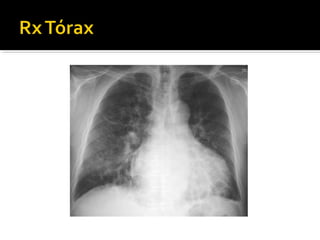

 Rx Tórax: puede ser normal en enf leve

 Imágenes sugestivas: bronquios dilatados

con paredes engrosadas, signo de “rail de

tranvia”, imagenes quísticas c/ o s/ niveles

hidroaereos

 Rx Tórax:puede ser normal en enf leve  Imágenes sugestivas: bronquios dilatados con paredes engrosadas, signo de “rail de tranvia”, imagenes quísticas c/ o s/ niveles hidroaereos